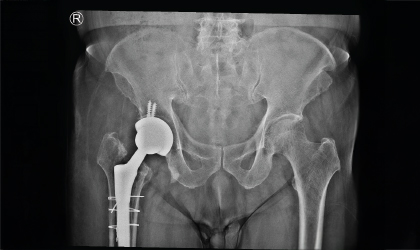

This 83 year old gentle man had a hip fracture 25 years ago. This became painful recently. He had an interesting (to the surgeons!) complication with a fracture of the stem in 3 places. This was revised to a total hip replacement. We used a longer stem to bypass the defects. He is mobile with a stick.

The patient’s old implant stem had fractured in three distinct places — a very rare and complex complication. This required careful planning for revision.